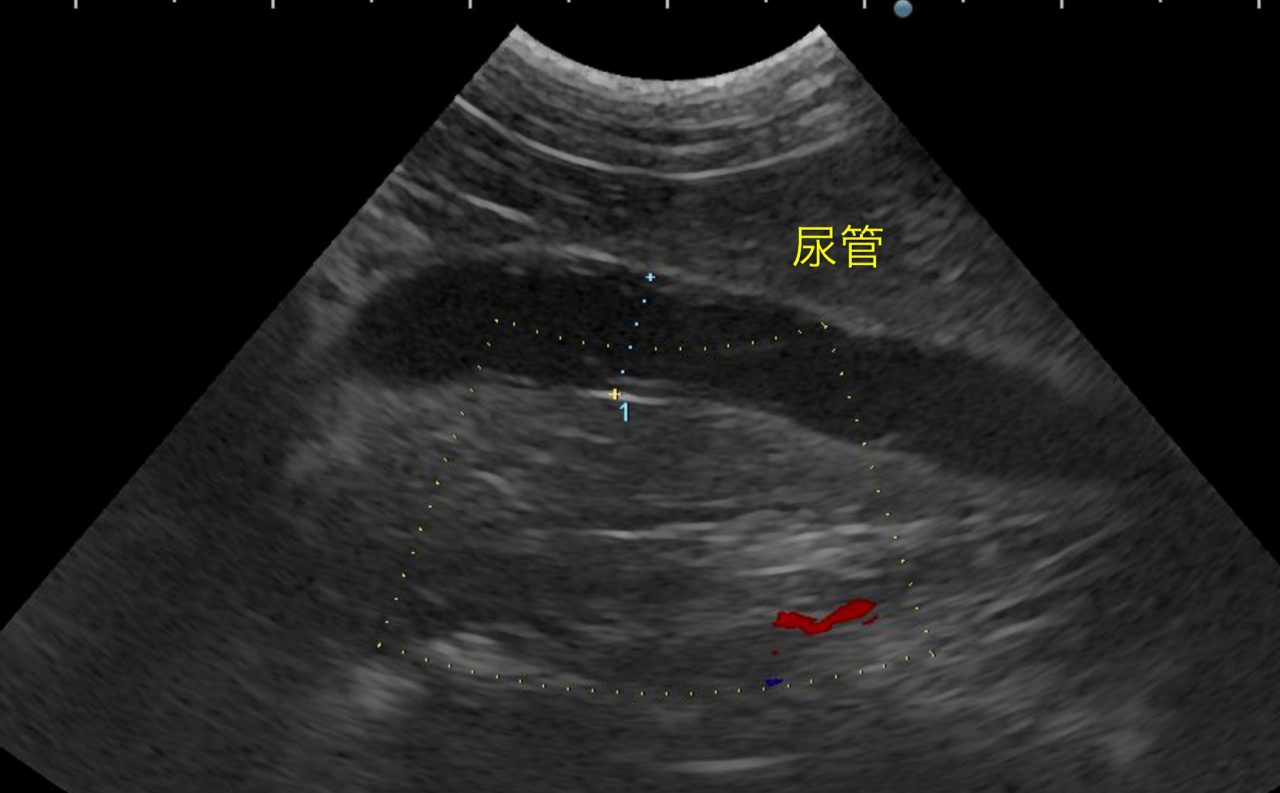

かかりつけ医で定期的に超音波検査で腎結石のモニターをしていたところ、急に腎盂が拡張してきたので早急に対応して欲しいと連絡がありました。尿管結石により尿路閉塞が起こっていました。マイクロサージェリーで尿管を2箇所切開し、尿管結石を摘除しました。術後の狭窄予防に一時的に尿管ステントを留置しています。術後翌日から、腎盂拡張は解消しましたが、術後の経過により、生体にとって異物となる尿管ステントは抜去する予定です。